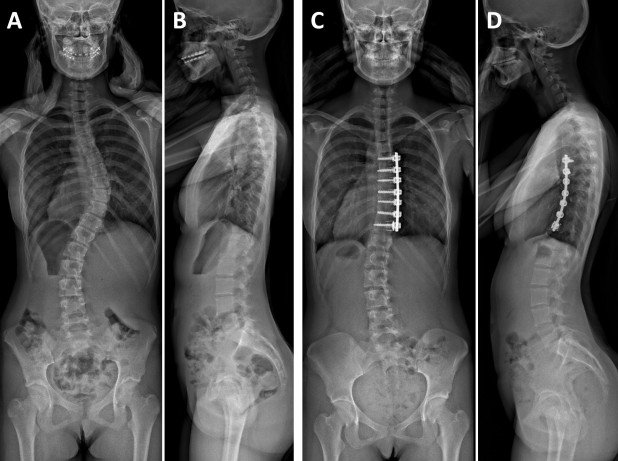

Vorderer Zugang bei Skoliose-Operation

Beim vorderen Zugang wird bei Skoliosen im Brustbereich ein seitlicher Hautschnitt entlang der Rippen (Thorakotomie), bei Skoliosen im Lendenbereich ein Hautschnitt in der Flanke (Lumbotomie, Thorako-Lumbotomie) getätigt. Die Rückenmuskulatur bleibt unberührt. Im Bereich der Hauptkurve wird die Wirbelsäulenverkrümmung mithilfe von Schrauben in den Wirbelkörpern und einem Verbindungsstab korrigiert und stabilisiert.